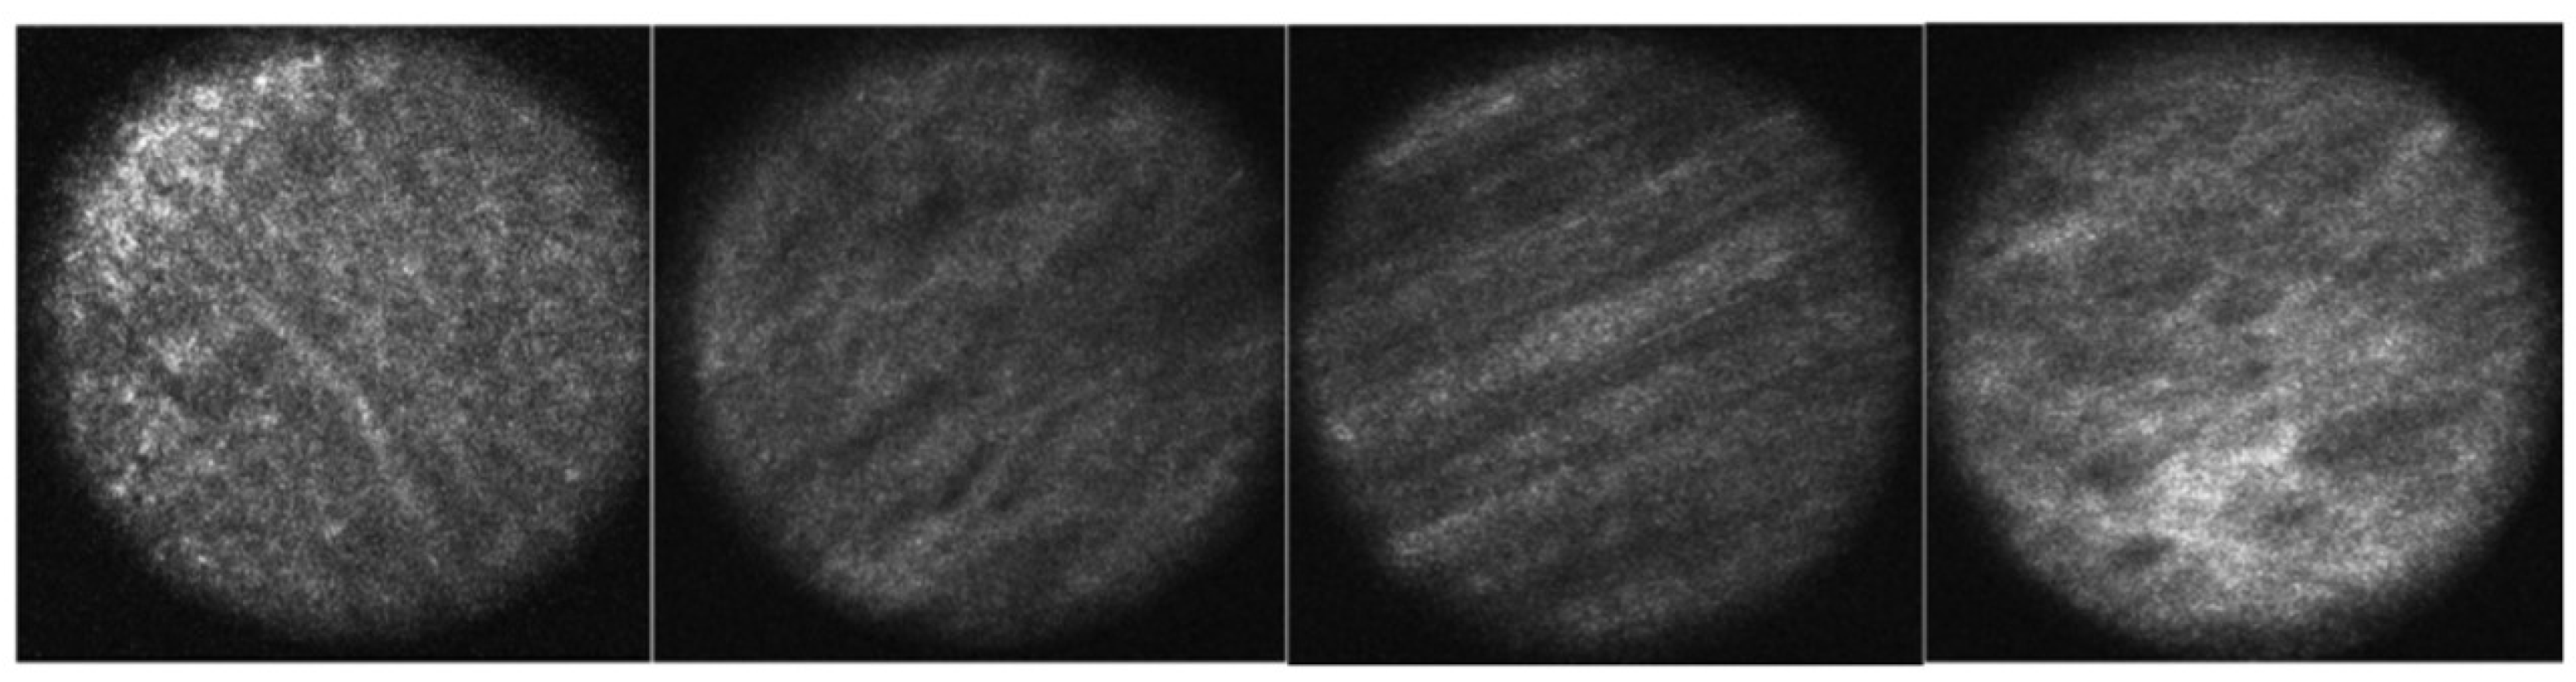

- Potluri, V.; Kathiresan, P.S.; Kandula, H.; Thirumalaraju, P.; Kanakasabapathy, M.K.; Pavan, S.K.S.; Yarravarapu, D.; Soundararajan, A.; Baskar, K.; Gupta, R.; et al. An inexpensive smartphone-based device for point-of-care ovulation testing. Lab Chip 2018, 19, 59–67. [Google Scholar] [CrossRef] [PubMed]

- Gessert, N.; Witting, L.; Drömann, D.; Keck, T.; Schlaefer, A.; Ellebrecht, D.B. Feasibility of Colon Cancer Detection in Confocal Laser Microscopy Images Using Convolution Neural Networks. In Bildverarbeitung für die Medizin; Springer Vieweg: Wiesbaden, Germany, 2019; pp. 327–332. [Google Scholar] [CrossRef]